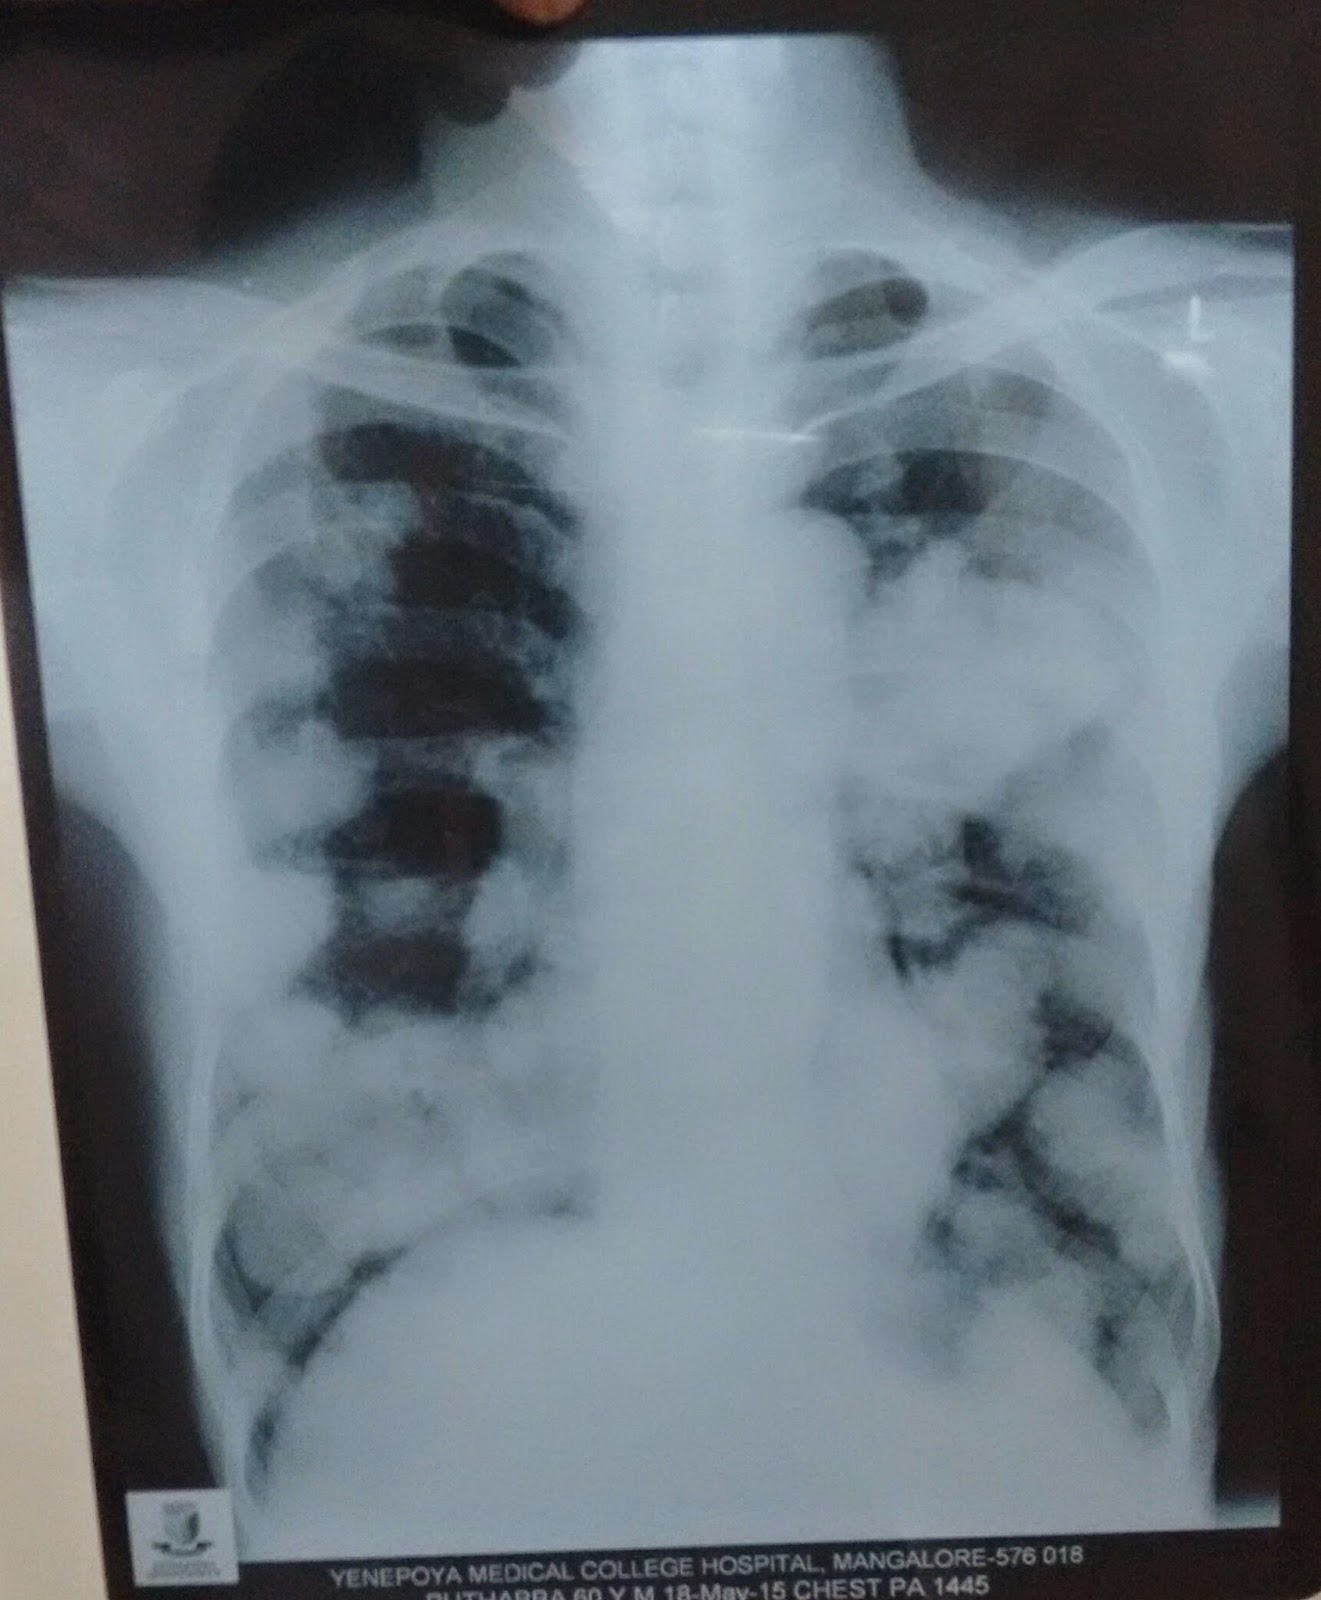

Chest Xray image. Polysegmental infiltration with tissue destruction